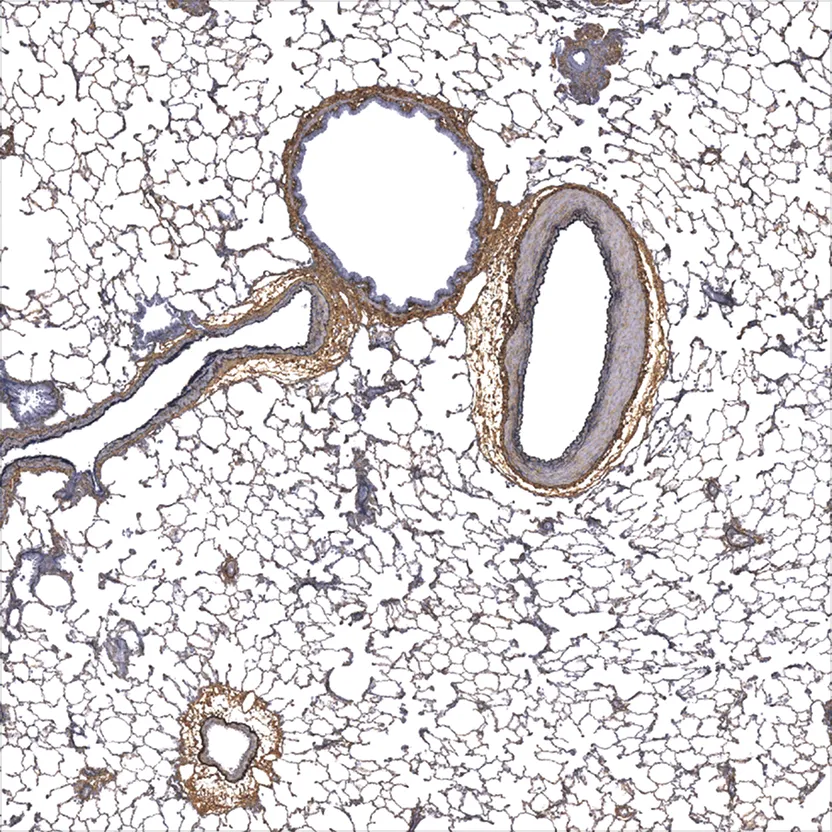

There are pros and cons to both chromogenic and fluorescent immunostaining methods. Chromogenic IHC can provide a scientist or pathologist more morphological context that can enhance interpretation. Moreover, chromogenic immunostaining is not light sensitive, and labeling will tend to not degrade over time or with exposure to light. Fluorescent immunostaining can be better in instances when it is necessary to co-stain for two or more targets, and a high level of co-localization is expected. The appropriate staining method will depend on the goals of the specific project.